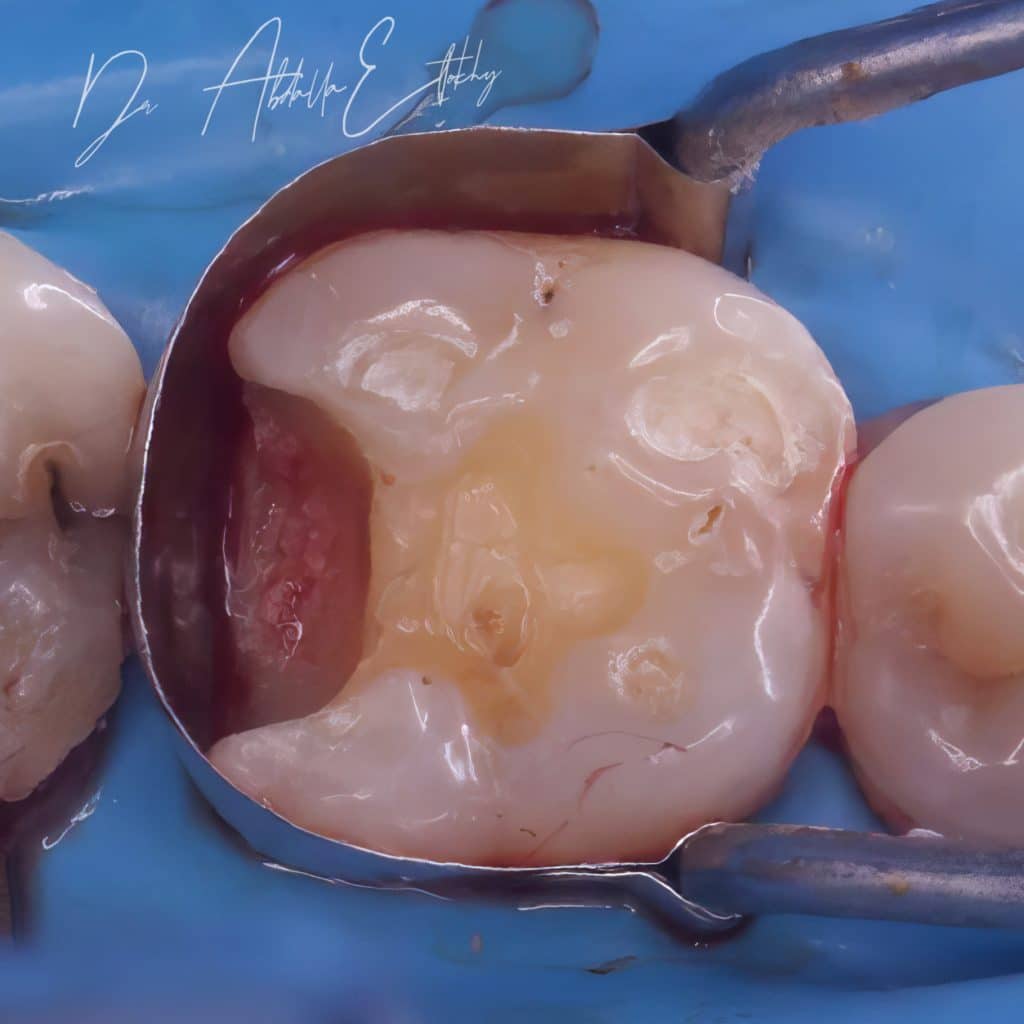

After clinical diagnosis & preoperative x-ray caries was close to the pulp but after taking history and doing vitality test with endo ice pt was suffering from hypremia so I started removing caries and selective caries removal was done to avoid pulp exposure then after getting a seal and drying cavity from bleed and doing etch and bond, small amount of flowable and packable was applied to ensure sealing and then RC was done then I waited about 5 min for maturation of hyprid layer then I continue elevating the margin and the restoration